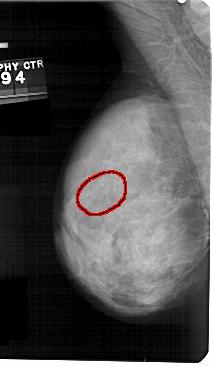

FILE: A_1326_1.LEFT_MLO.OVERLAY

TOTAL_ABNORMALITIES 1

ABNORMALITY 1

LESION_TYPE CALCIFICATION TYPE PLEOMORPHIC DISTRIBUTION LINEAR

ASSESSMENT 4

SUBTLETY 4

PATHOLOGY BENIGN

TOTAL_OUTLINES 1

BOUNDARY